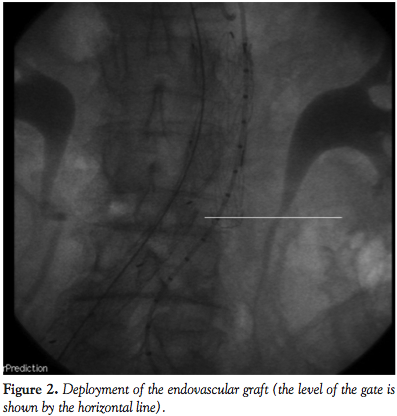

After baseline angiography and positioning of an 0.35 Amplatz Superstiff wire (Boston Scientific) in the aortic arch, an 28 x 140 cm Gore Excluder EVG body (W. L. Gore & Associates) (Figures 1 and 2) was deployed immediately below the lower renal artery. Then, controlateral gate was cannulated by means of a 260 cm 0.035-inch Radifocus wire (Terumo) and a multipurpose (Cordis). The Radifocus wire was exchanged for an Amplatz Superstiff wire and a 18 Fr sheath was carefully advanced to reach the gate region for contralateral deployment of a 18 x 10 cm leg.